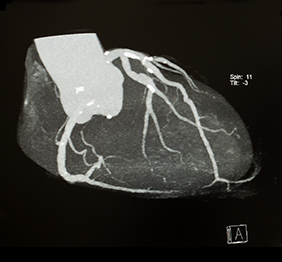

Angiocoronarografia CT

Investigatie imagistica non-invaziva a cordului si arterelor coronare - artere care vascularizeaza muschiul cardiac, fiind o alternativa la coronarografia clasica